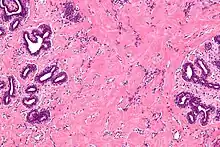

| High magnification micrograph of pseudoangiomatous stromal hyperplasia showing the characteristic small, anastomosing blood vessel-like channels. H&E stain. | |

Pseudoangiomatous stromal hyperplasia (PASH) is an overgrowth of myofibroblastic cells in the breast. It has an appearance similar to fibroadenomatoid changes.[1]